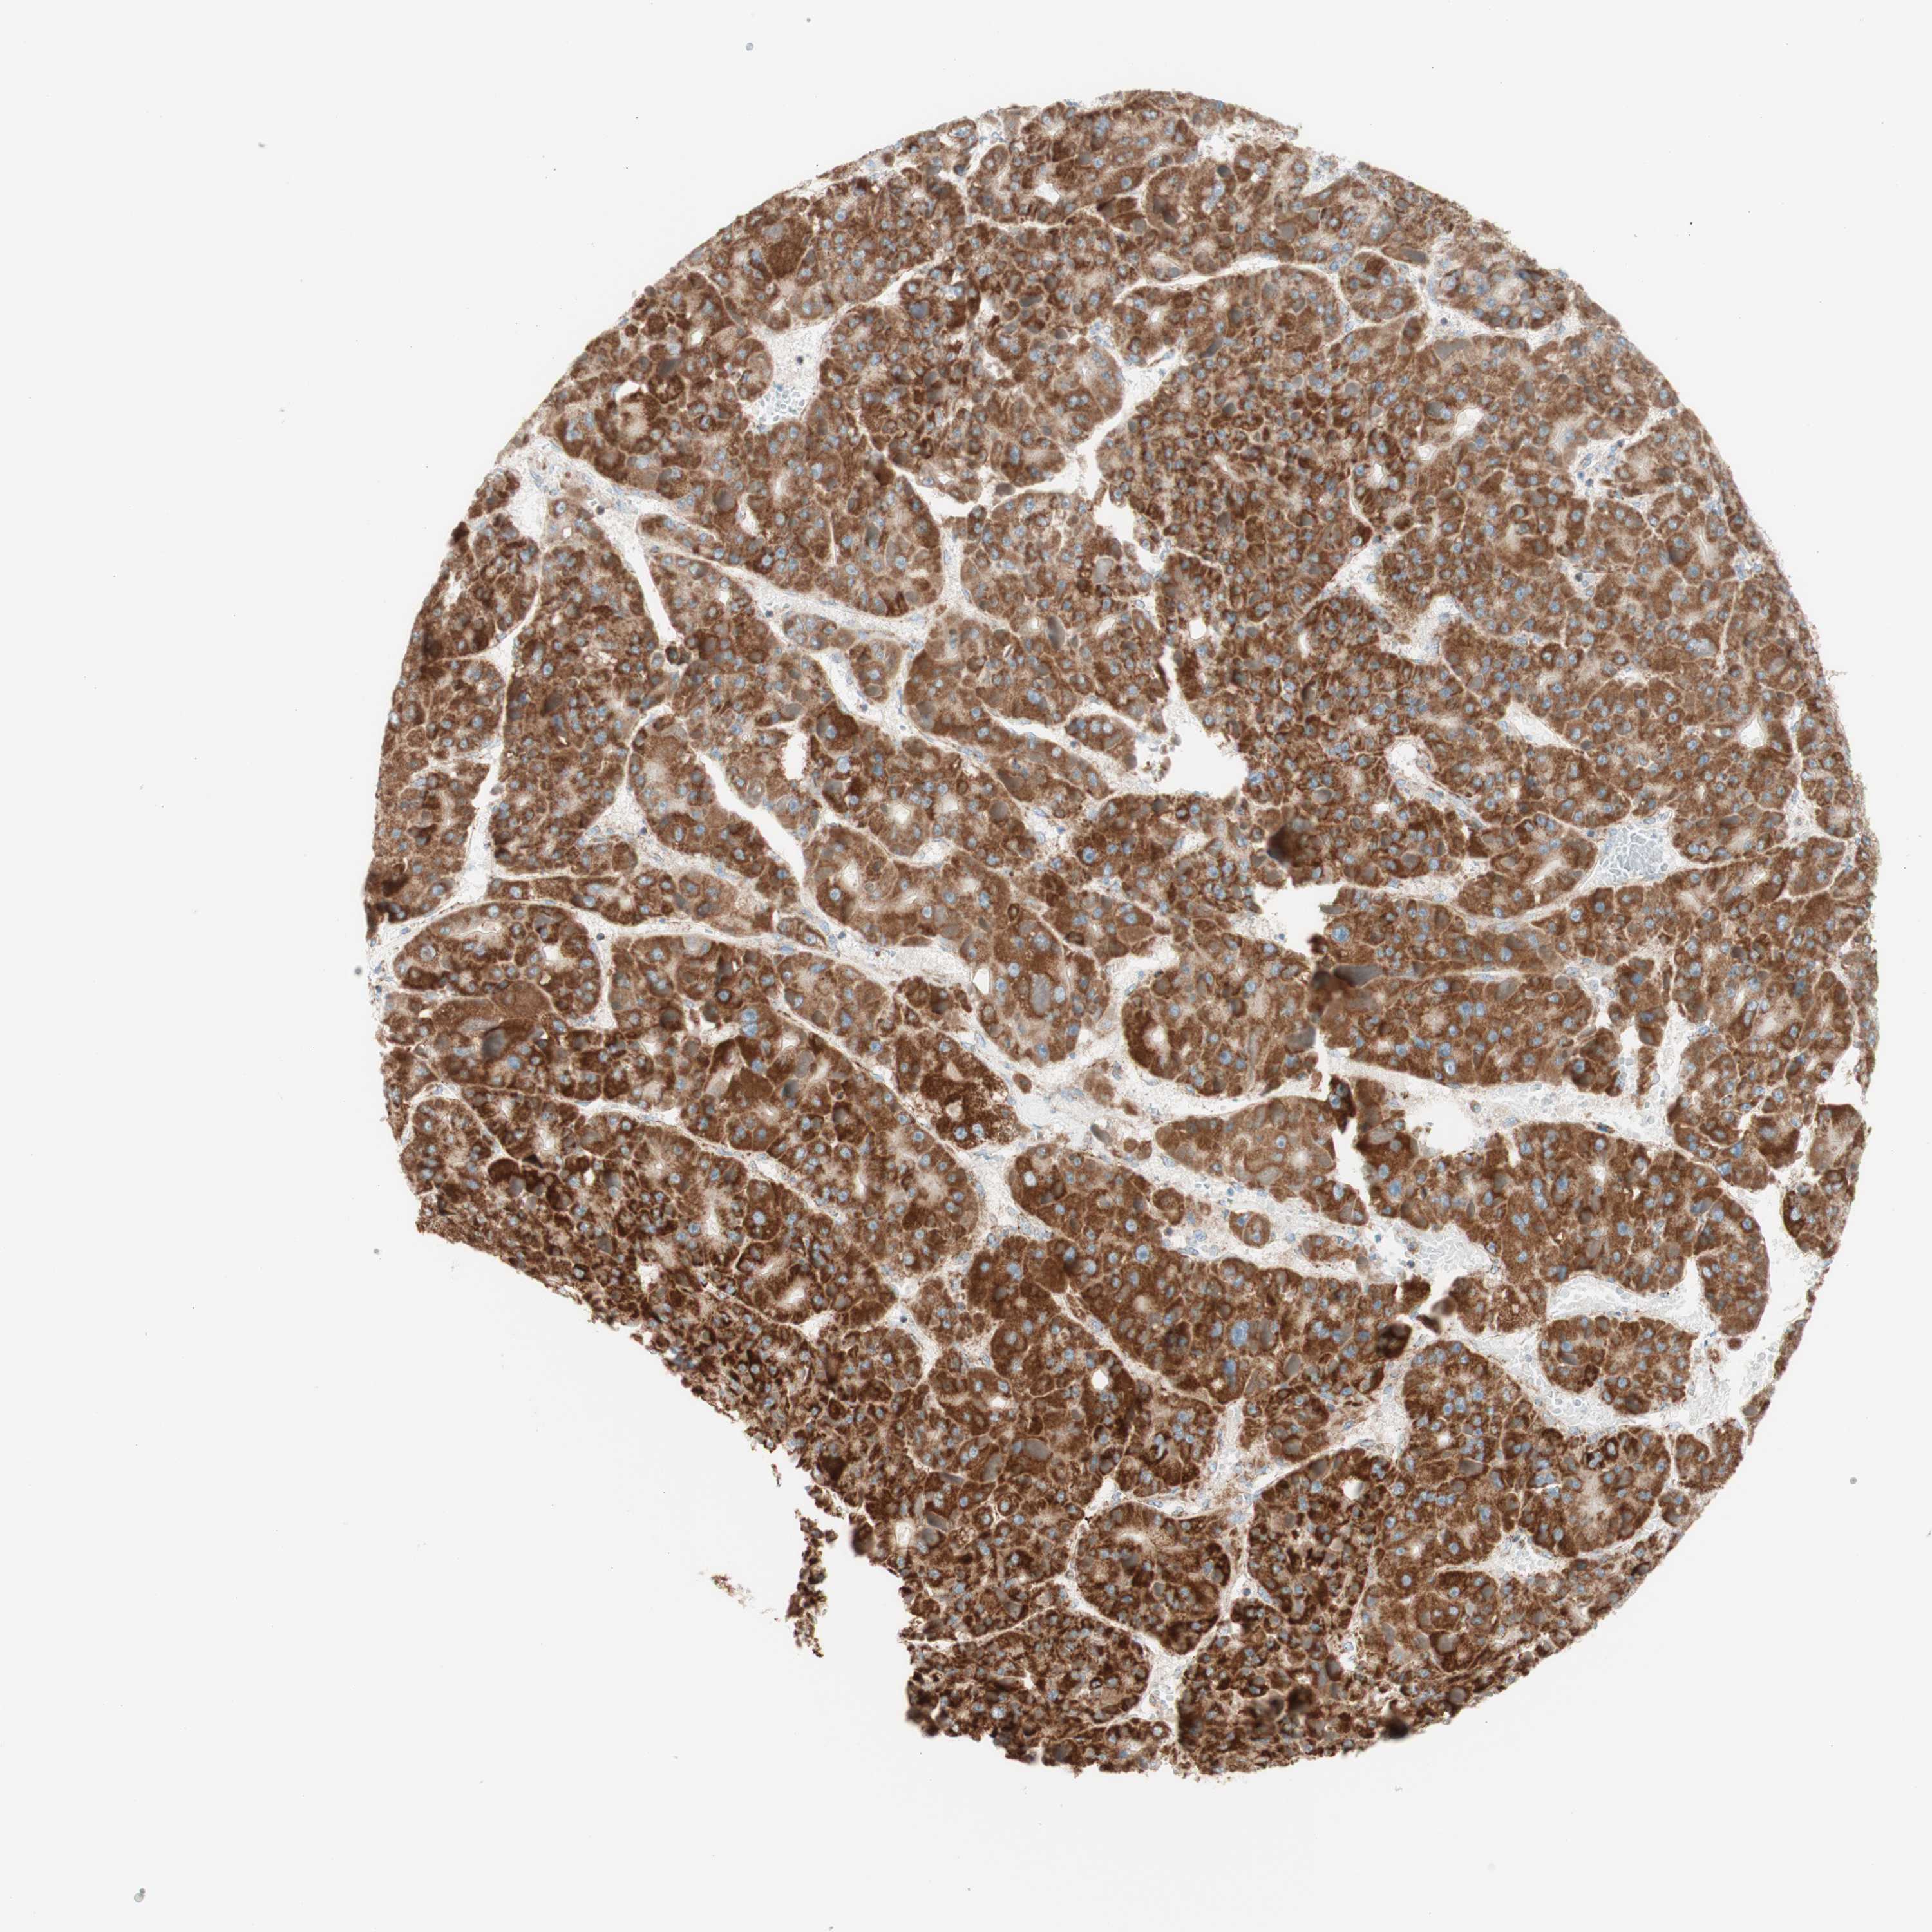

LIVER CANCER - Protein expressioni

A mouse-over function shows sample information and annotation data. Click on an image to view it in a full screen mode. Samples can be filtered based on level of antibody staining by selecting one or several of the following categories: high, medium, low and not detected. The assay and annotation is described here.

Note that samples used for immunohistochemistry by the Human Protein Atlas do not correspond to samples in the TCGA dataset.

Antibody stainingi

Antibody staining in the annotated cell types in the current human tissue is reported as not detected, low, medium, or high, based on conventional immunohistochemistry profiling in selected tissues. This score is based on the combination of the staining intensity and fraction of stained cells.

Each image is clickable and will lead to virtual microscopy that enables deeper exploration of all samples and also displays staining intensity scores, fraction scores and subcellular localization as well as patient and tissue information for each sample.

Antibody HPA011562

Antibody CAB005585

Staining

High

Medium

Low

Not detected

Intensity

Strong

Moderate

Weak

Negative

Quantity

>75%

75%-25%

<25%

None

Location

Nuclear

Cytoplasmic/membranous

Cytoplasmic/membranous,nuclear

Cholangiocarcinoma

Carcinoma, Hepatocellular, NOS